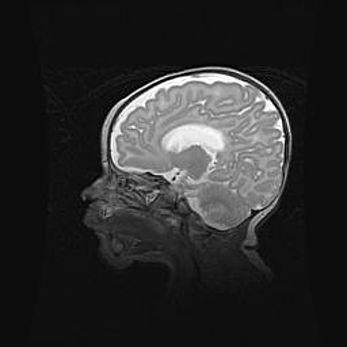

Церебральная ишемия II.

Возраст: 5 дней

Вес: 3400 г

Пол: женский

Окружность головы: 35 см

Срок гестации: 39 недель

Церебральная ишемия – это заболевание, характеризующееся недостаточностью (гипоксией) либо полным прекращением (аноксией) снабжения мозга кислородом по причине закупорки одного или нескольких сосудов. Это приводит к  что метаболическим расстройствам различной степени тяжести в тканях головного мозга, развитию коагуляционных некрозов и гибели нейронов.